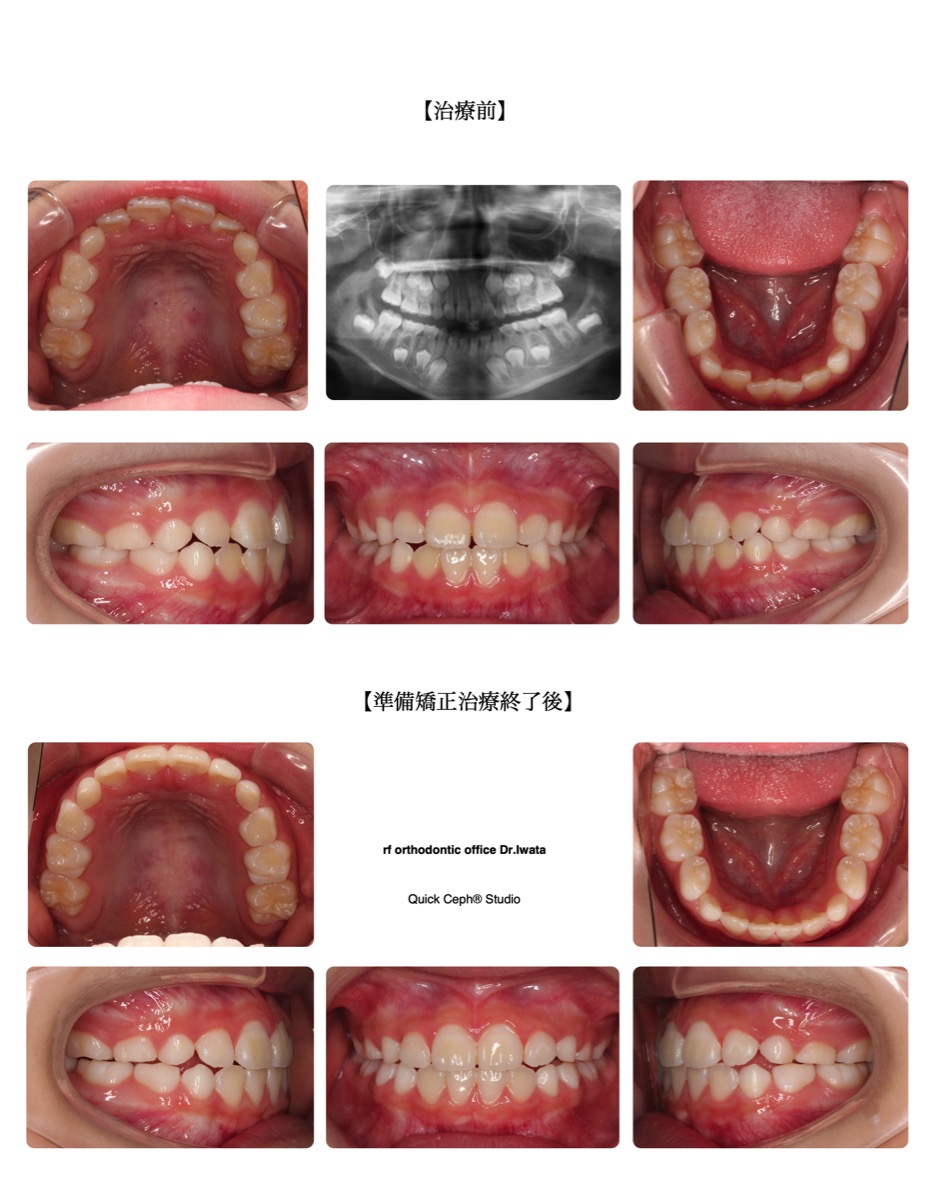

case1

叢生(でこぼこ)

歯が一列に並びきらず、デコボコになっている噛み合わせ。

治療症例

case study

症例数においては過去5,203件以上※。当クリニックでおこなった矯正治療症例を一部ご紹介いたします。